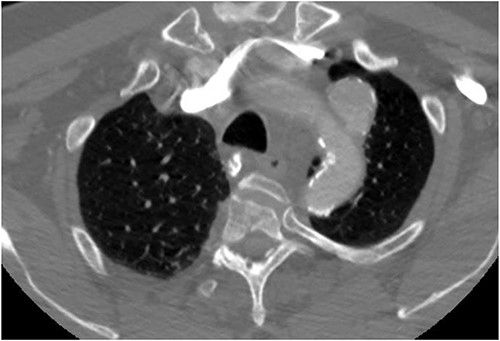

The patient is a 70-year-old male with an incidental finding of a proximal LSA aneurysm on computed tomography (CT) angiography of the chest performed for shortness of breath. He had no dysphagia, neurologic or vascular occlusive symptoms. He had no history of trauma or known congenital anomaly. The aneurysm had a maximal diameter of 3.4 cm and was located at the origin of the artery (Fig. 1). An aberrant left vertebral artery and hypoplastic right vertebral artery were also identified. The left vertebral artery originated from the aortic arch proximal to the LSA takeoff (Fig. 2) and provided dominant posterior cerebral circulation.

Preoperative CTA demonstrating aberrant left vertebral artery originating from the aortic arch, just proximal to the LSA.